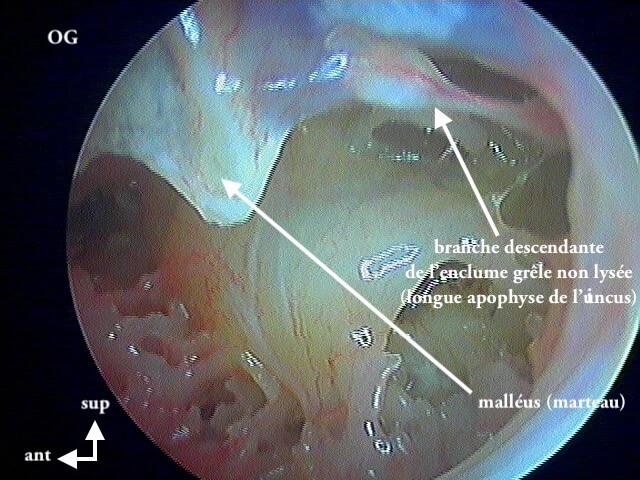

9 OTITE MOYENNE CHRONIQUE (OMC) NON CHOLESTÉATOMATEUSE

Perforation , otorrhée à répétition, otite muqueuse dans la caisse, lyse ossiculaire, rétraction tympanique. La limite entre l'otite atéléctasique perforée et l'otite moyenne chronique non cholestéatomateuse est souvent ésotérique...